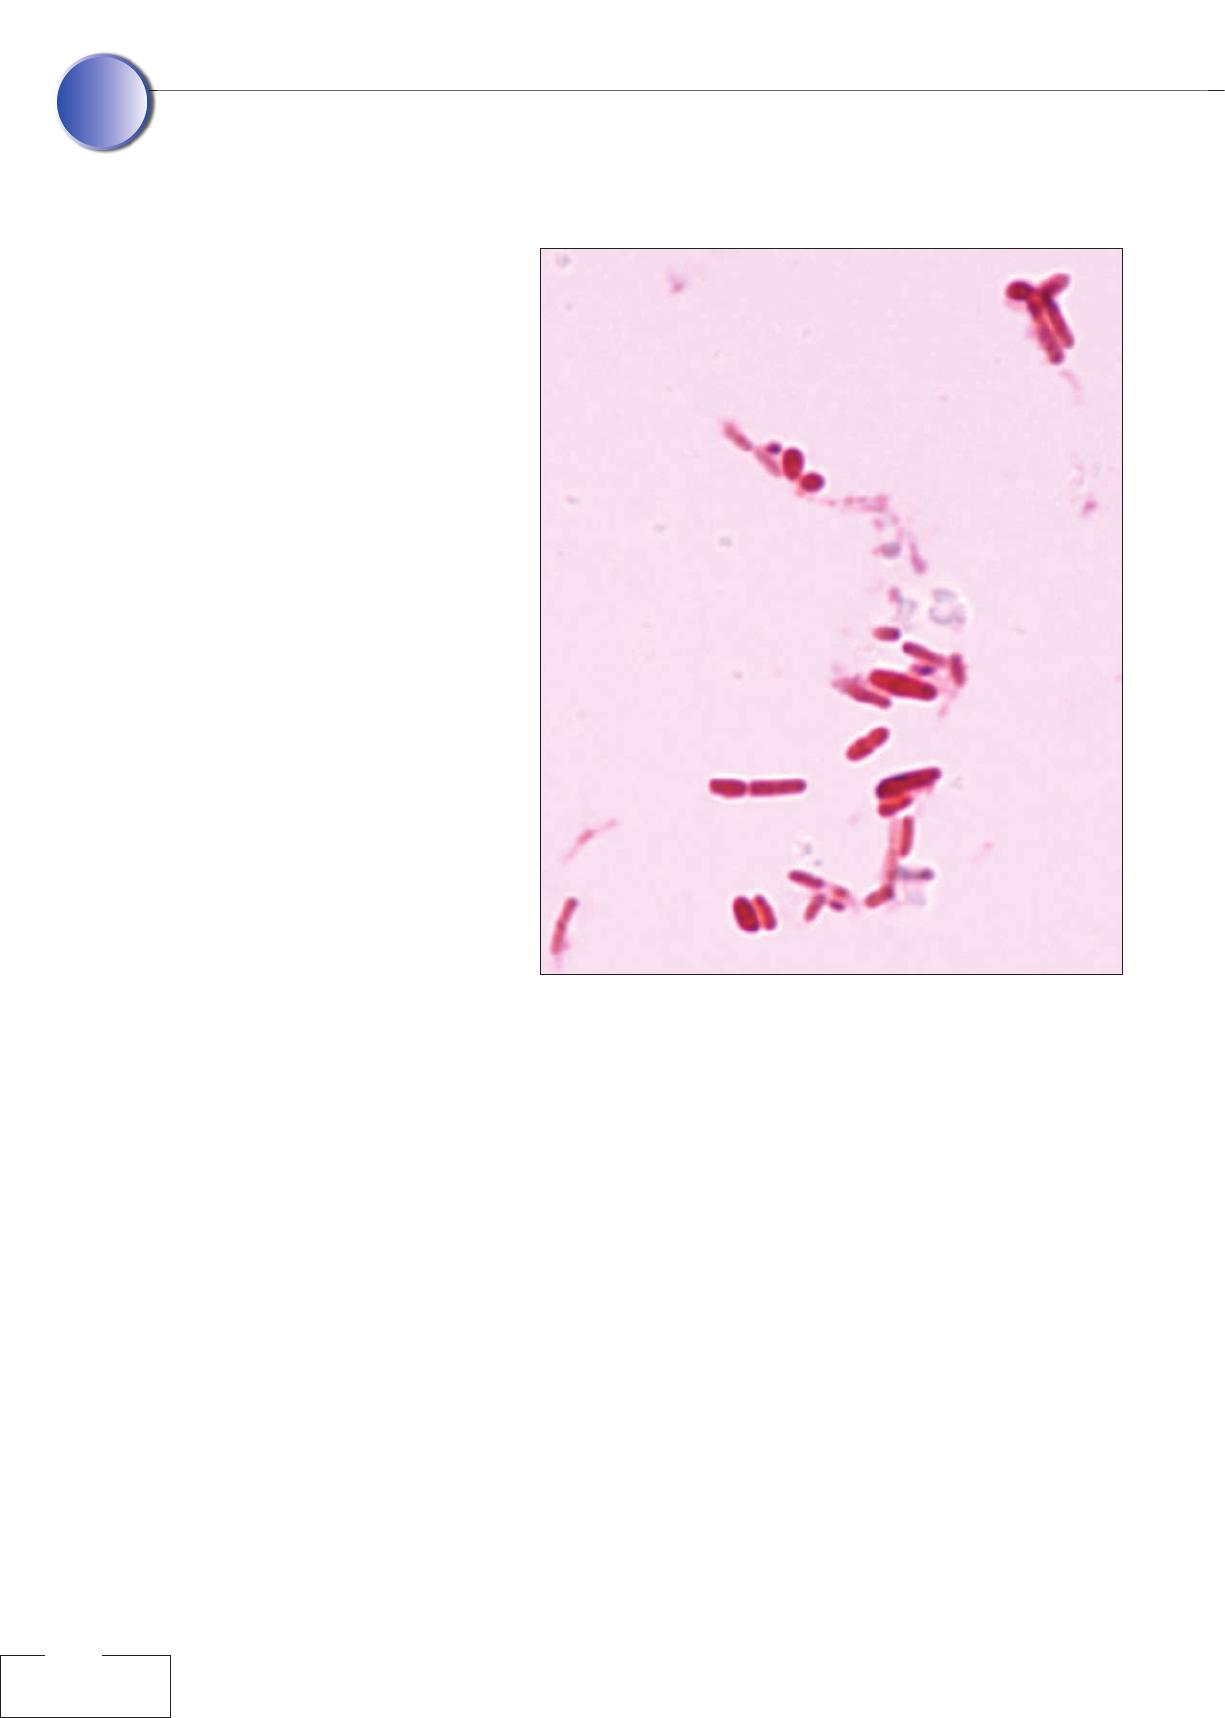

Figure 3

Arbre phylogénétique de

la souche C. xerosis CIP

108444.

dant l’étude du gène rrs de l’ARNr 16 S montre une

homologie de séquence supérieure à 98 % avec C.

freneyi (quatre souches connues) et C. xerosis mais

s’avère insuffisante pour les différencier (figure 3).